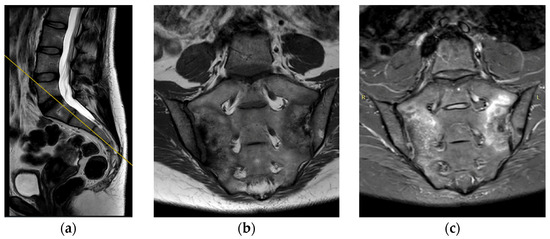

The deviation angles were measured on T2-weighted sequence slices obtained in the sagittal plane, as shown in Figure 1. Figure 2, presented below, shows the interrelationship of the three sequences of the same examination (as shown in Figure 1) that were used in this study. The RadiAnt DICOM Viewer was used to take measurements. All examinations were analyzed by two independent researchers in a blind study. The final results of the measurements were averaged to obtain a single deviation angle corresponding to each examination.

Figure 2.

(a) Example of sagittal T2 series. Yellow line indicates the position of coronal projections (b,c). (b) Example of coronal T2 series. (c) Example of coronal STIR series.